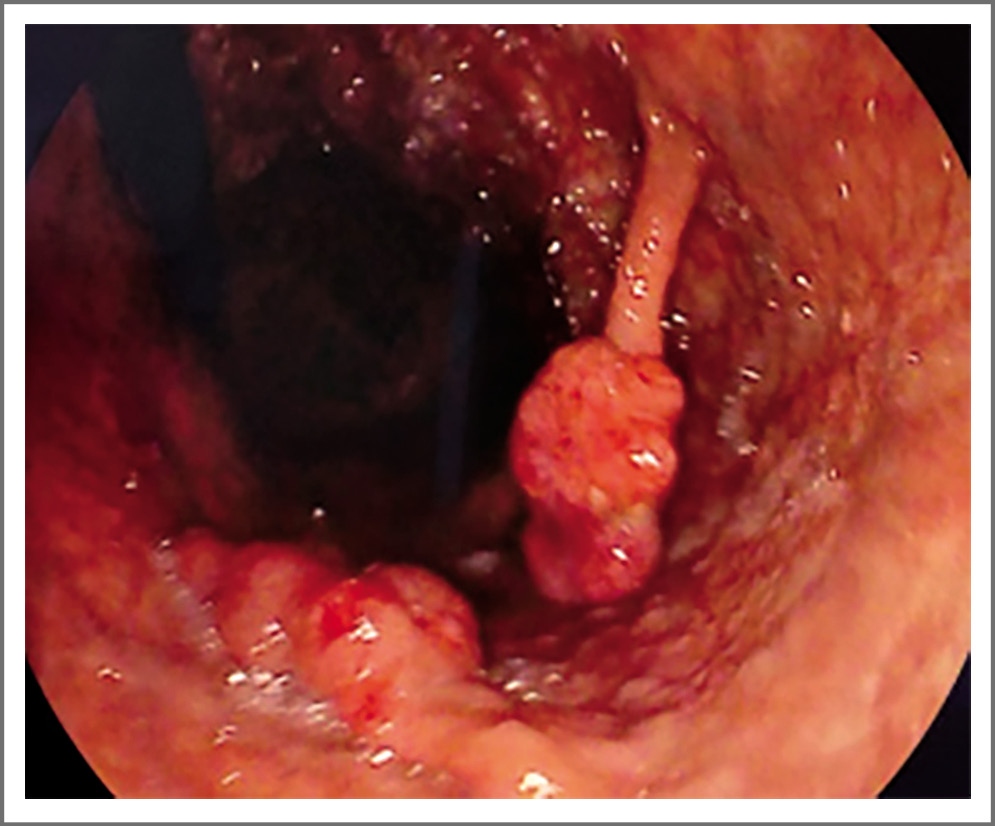

При отсутствии инвагинатов 9/30 (30%) пациентам, в том числе и 2 пациентам, у которых не выявлены полипы тонкой кишки при лучевых методах исследования, выполнена видеокапсульная эндоскопия, по данным которой у всех 9 пациентов имелись множественные (более 20) полипы тонкой кишки диаметром 0,5–15 мм. Данная находка на тактику лечения никак не повлияла, однако эти пациенты требуют более частого обследования (1 раз в 6 мес) для оценки интенсивности роста полипов и своевременного удаления наиболее крупных гамартом. Таким образом, у всех пациентов отмечено поражение тонкой кишки, тогда как в желудке полипы выявлялись у 23/30 (77%) пациентов (рис. 2), а в толстой кишке – у 21/30 (70%). В ходе дальнейшего наблюдения отмечался рост новых полипов как в желудке, так и в толстой кишке (табл. 3).

Рис. 2. Эзофагогастродуоденоскопия, гамартомный полип желудка до 2,5 см в диаметре. / Fig. 2. Esophagogastroduodenoscopy, hamartomatous polyp of the stomach up to 2.5 cm in diameter.